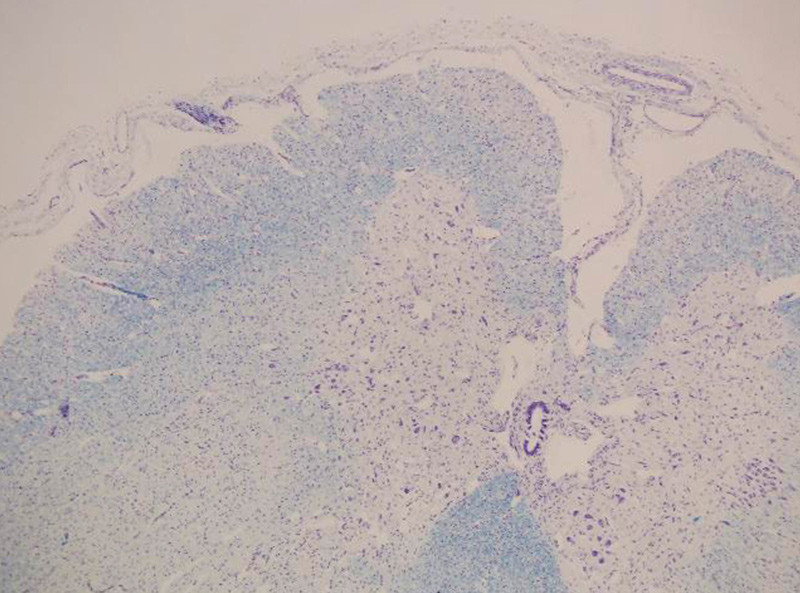

Ved obduksjon var det normale funn i hjerne, lillehjerne og hjernestamme. Diafragma var løvtynn, og i snitt fra diafragma og muskulatur i over- og underekstremiteter fantes en uttalt storgruppeatrofi. Primært ble det ikke beskrevet svinn av nerveceller i medulla spinalis.

2 1/2 år senere beskrev en annen nevropatolog nervecellesvinn i de motoriske forhorn i torakalmedulla, med fibersvinn i fremre røtter. Det var ikke fibersvinn i sensoriske røtter. Snitt fra perifere nerver viste fibrose og bare enkelte myeliniserte fibre. Det var ingen holdepunkter for Guillain-Barrés syndrom.

Ved obduksjon ble det funnet tynn diafragma, på kun 1 – 2 mm. Det var svinn av forhornceller i medulla spinalis (fig 1), med usedvanlig små fremre røtter (fig 2). Det var også mulig fibersvinn i kortikospinale baner gjennom hele hjernestammen og i tractus corticospinalis lateralt i medulla. I diafragma fantes spredte grupper av atrofiske fibre og spredte hypertrofiske fibre (fig 3). I skjelettmuskulatur fantes områder med muskelatrofi (fig 4). Det ble fortsatt konkludert med en variant av Werdnig-Hoffmanns sykdom.

De nevropatologiske funn hos disse pasientene varierer. Hos alle finner man muskelatrofi, og mange beskriver forandringer i perifere nerver. Selv om tilstanden oppfattes som spinal muskelatrofi, har ikke alle funnet de forandringer i medullas forhornceller som man ville vente (7). Hos våre pasienter som ble undersøkt, beskrives svinn av nevroner. Både nevropatologiske funn og nevrofysiologiske resultater tyder på perifer aksonal affeksjon og/eller progredierende affeksjon av både motoriske og sensoriske nevroner, der motoriske nevroner blir tidligst og mest affisert.